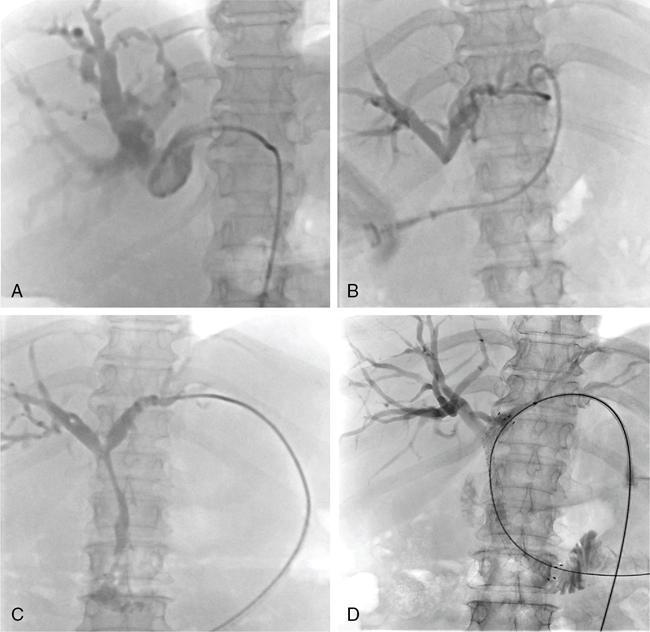

In patients with unresectable malignant biliary obstruction, biliary drainage provides palliation. External or combined internal–external drainage PTBD catheter is uncomfortable for the patient, requires constant care and causes psychological discomfort. Catheter-related complications such as pericatheter leak, tube blockage and kinking and dislodgement occur frequently and add to the morbidity of the patient. Placement of a stent for internal drainage overcomes these complications. Indications for metallic stents include malignant biliary obstruction, mostly in nonresectable cases. Uncommonly, retrievable stents are also placed for BBSs. Stents may be placed intrahepatically for tumours beyond hilum (unilateral or bilateral), in the bile duct and even as bowel stents where tumours invade the gastrointestinal tract beyond ductal entry. There are no absolute contraindications for biliary stenting. Relative contraindications are similar to that for PTBD. Preprocedure imaging is important to identify the type and location of the malignancy. This often helps to decide whether unilobar (Fig. 9.24.12) or bilobar stent (Fig. 9.24.13) is needed. It also helps to define the length of the stricture, although, length of the stent is based on cholangiographic measurements. Further, imaging is important to confirm that the disease is unresectable, as placement of stent makes surgery challenging in resectable cases. Patient preparation is similar to that for PTBD. The initial steps are same as for PTBD till the point of internalization. Then, either the stent is placed as a primary procedure or later as a secondary procedure. After placement of a stiff guidewire, the stent device is inserted over it. The ideal position of the stent is when its proximal and distal ends extend at least 1 cm and preferably 2 cm from the proximal and distal ends of the stricture, respectively. After stenting, an access catheter (5F) is usually placed in situ and the stent is evaluated with a cholangiogram after 48 hours. The metallic stent self-expands and allows internal biliary drainage with resultant decompression of the biliary system. The self-expanding metal stents are made of nitinol, and have thermal memory, allowing them to expand to their maximum diameter when they reach body temperature. This usually occurs in 24–48 hours. In cases, where the stent fails to expand adequately even after 48 hours, percutaneous balloon dilatation of the stent through the access catheter should be done for successful drainage. There are two broad categories of stents: plastic and metallic. Metallic stents can further be divided as covered and uncovered. Plastic stents are placed endoscopically and generally used for benign strictures. They have lower patency rates, require longer hospital stay and a higher overall cost, making them less suitable as palliative stents. Stent-related complications are being increasingly recognized due to the increased life expectancy of patients with stent insertions. This is attributed to the improved palliative care and management of these patients. The complications can be divided into early and delayed (Table 9.24.4).